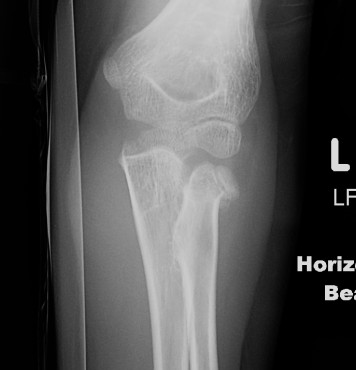

FOOSH

- valgus injury

- don't get radial head fracture as is mostly cartilaginous

Types

SH 1 or 2